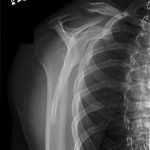

Radiographs demonstrated posterior displacement of the humeral head on the “Y” view (see white arrow) and widening of the glenohumeral joint space on anterior-posterior view (see red arrow). The findings were consistent with posterior dislocation and a Hill-Sachs type deformity. Sedation was performed and reduction was attempted using external rotation, traction counter-traction. An immediate “pop” was felt during the procedure. Post-procedure radiographs revealed a persistent posterior subluxation with interlocking at posterior glenoid. CT revealed posterior dislocation with acute depressed impaction deformity medial to the biceps groove with the humeral head perched on the posterior glenoid, interlocked at reverse Hill-Sachs deformity (see blue arrow).

Posterior shoulder dislocations are rare and represent only 2% of all shoulder dislocations. Posterior shoulder dislocations are missed on initial diagnosis in more than 60% of cases.1 Posterior shoulder dislocations result from axial loading of the adducted and internally rotated shoulder, violent muscle contractions (resulting from seizures or electrocution), a direct posterior force applied to the anterior shoulder.1 Physical findings include decreased anterior prominence of the humeral head, increased palpable posterior prominence of the humeral head below the acromion, increased palpable prominence of the coracoid, marked limitation of abduction, and complete absence of external rotation with a fixed internal rotation deformity.2 Lesions commonly associated with traumatic posterior subluxation/dislocation are the reverse Hill-Sachs,3 a posterior labral detachment, glenohumeral ligament lesions,4 rotator cuff tears or posterior bony fractures.1 In order to make an accurate diagnosis it is important to obtain adequate x-ray imaging, including a “Y” view.2 Anteroposterior x-rays may show widening of the glenohumeral joint resembling a “light bulb” shape of the humeral head. However, definitive diagnosis is made by the “Y” view which shows the humeral head displaced posteriorly and no longer covering the glenoid fossa6. Irreducible acute posterior dislocation of the shoulder is extremely rare5 and only one other case has been reported in the literature.7